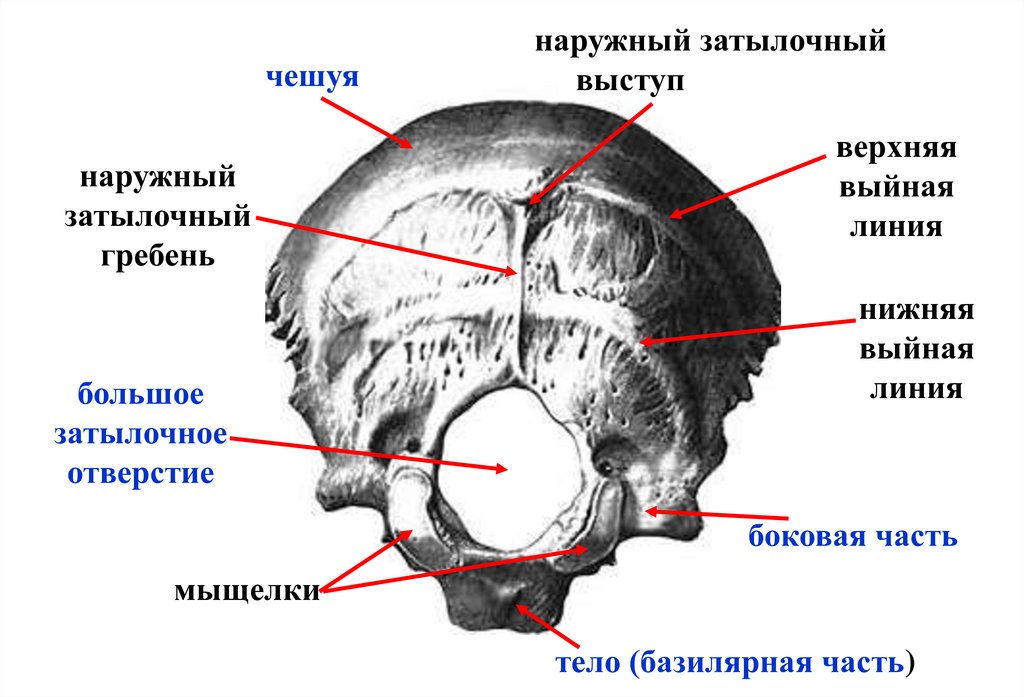

Анатомические изображения срединной сагиттальной линии черепа

Раздел: Образы вокруг